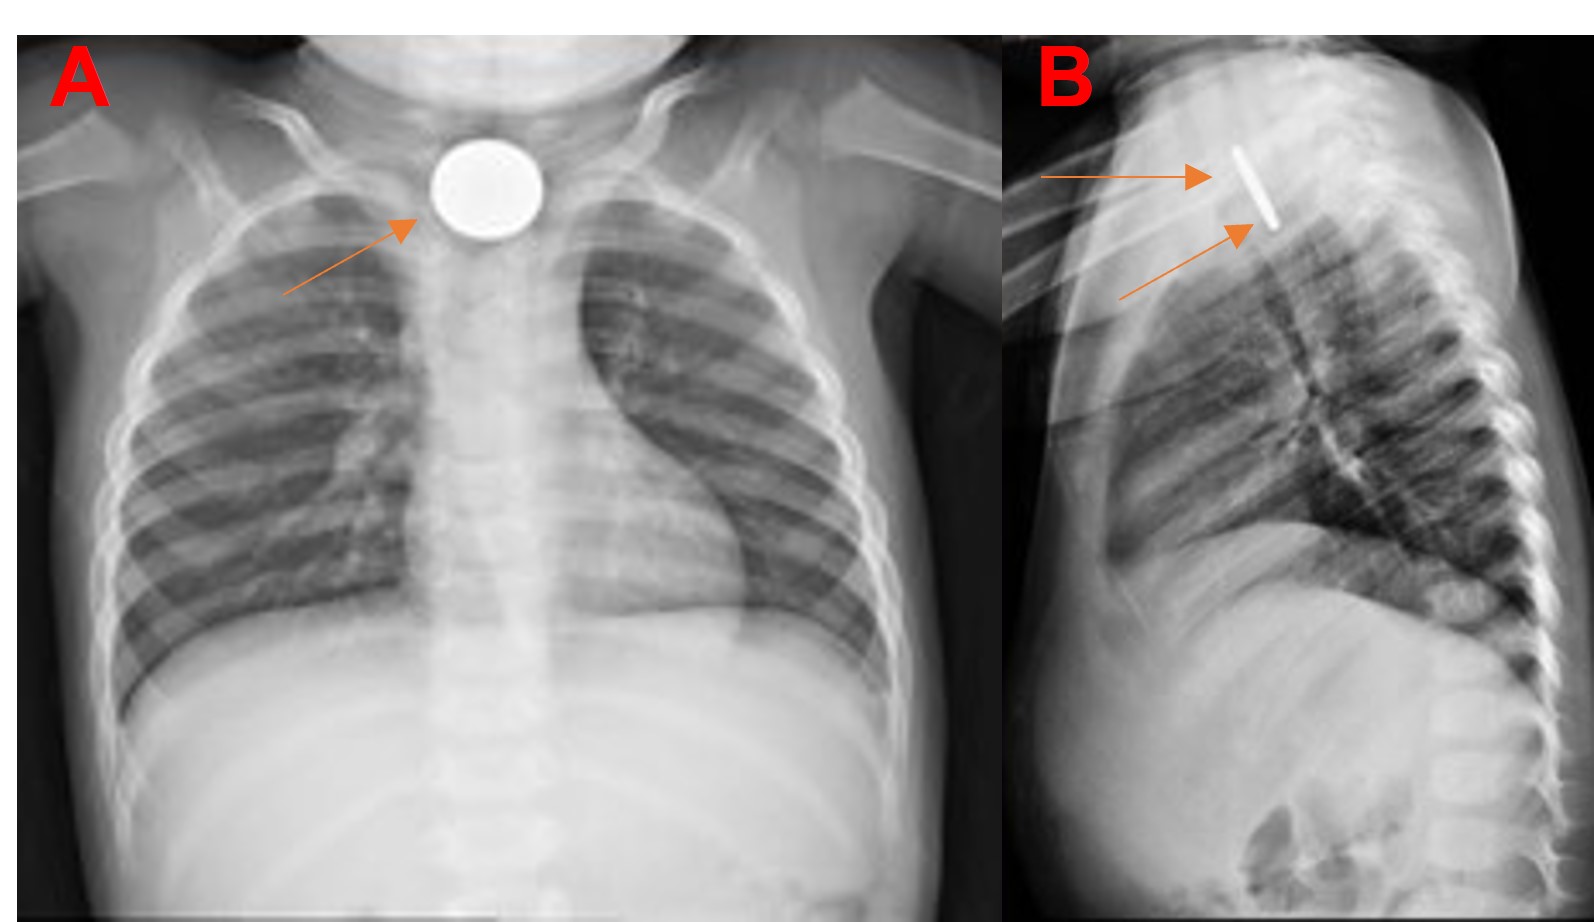

Diagnóstico tardío de ingestión de cuerpo extraño en un niño: reporte de caso

Jorge Enrique Guzmán Vélez, Melissa Navarro Holguín, Daniela Montoya Rúa, Manuela Lince Restrepo

12-15